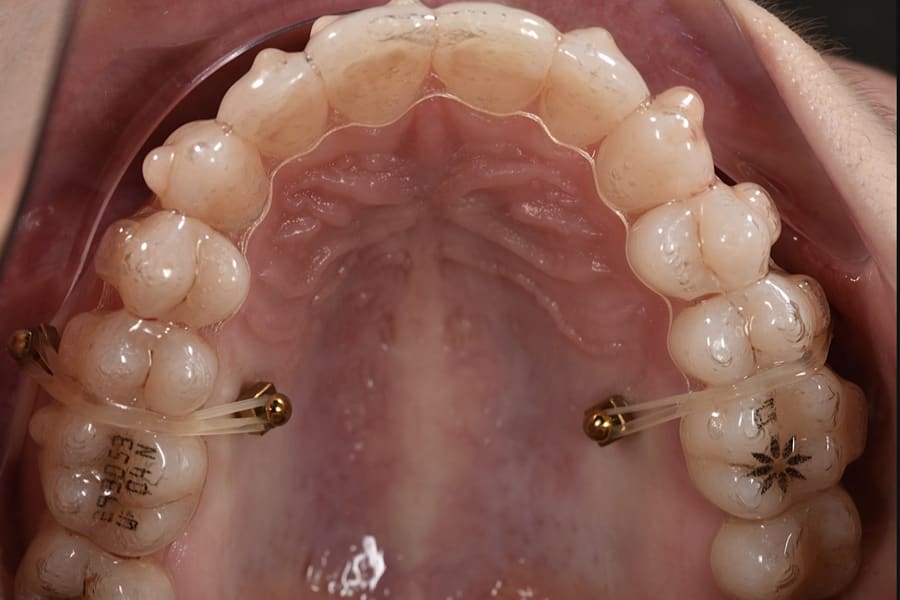

The orthodontic biomechanics are as follows: Skeletally anchored buccal and palatal TADs are positioned between the second premolar and first molar to provide vertical anchorage. Clear aligners are used for dental and dentoalveolar movement and remodeling to deliver controlled derotation, torque, curve-of-Spee adjustment, and anchorage-friendly staging. Elastics or chains to TADs add cranially directed force vectors for intrusion. Anterior vertical position is maintained to protect smile esthetics.3,7,17-21

A 31-year-old female patient presented with the following intraoral conditions: an anterior open bite, bimaxillary crowding, negative crown torque, early “black triangles,” and a thin phenotype/biotype with early recessions. Her extraoral situation included a gummy smile with high-lip mobility, asymmetric arch forms and posterior corridors, and incompetent lip closure (Figure 2 through Figure 4). Collectively, these factors increase esthetic and periodontal risk and favor posterior intrusion over anterior intrusion.4-8,12-16

Posterior intrusion (eg, approximately 2 mm to 3 mm molar intrusion) is modeled to define mandibular CCW autorotation, ensuring acceptable anterior guidance and envelope. Hybrid analog/digital or fully digital jaw-tracking/axiography improves precision for the terminal mandibular position at treatment completion.9-11 (Figure 10 through Figure 13)